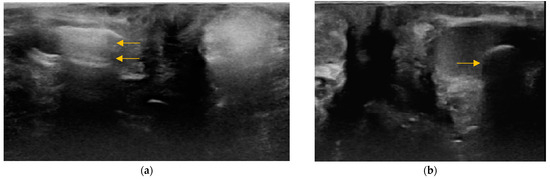

3.2. Content of Anal Sacs

3.3. Size and Shape of Anal Sacs

3.4. Wall of Anal Sacs

3.5. Adverse Findings

4. Discussion